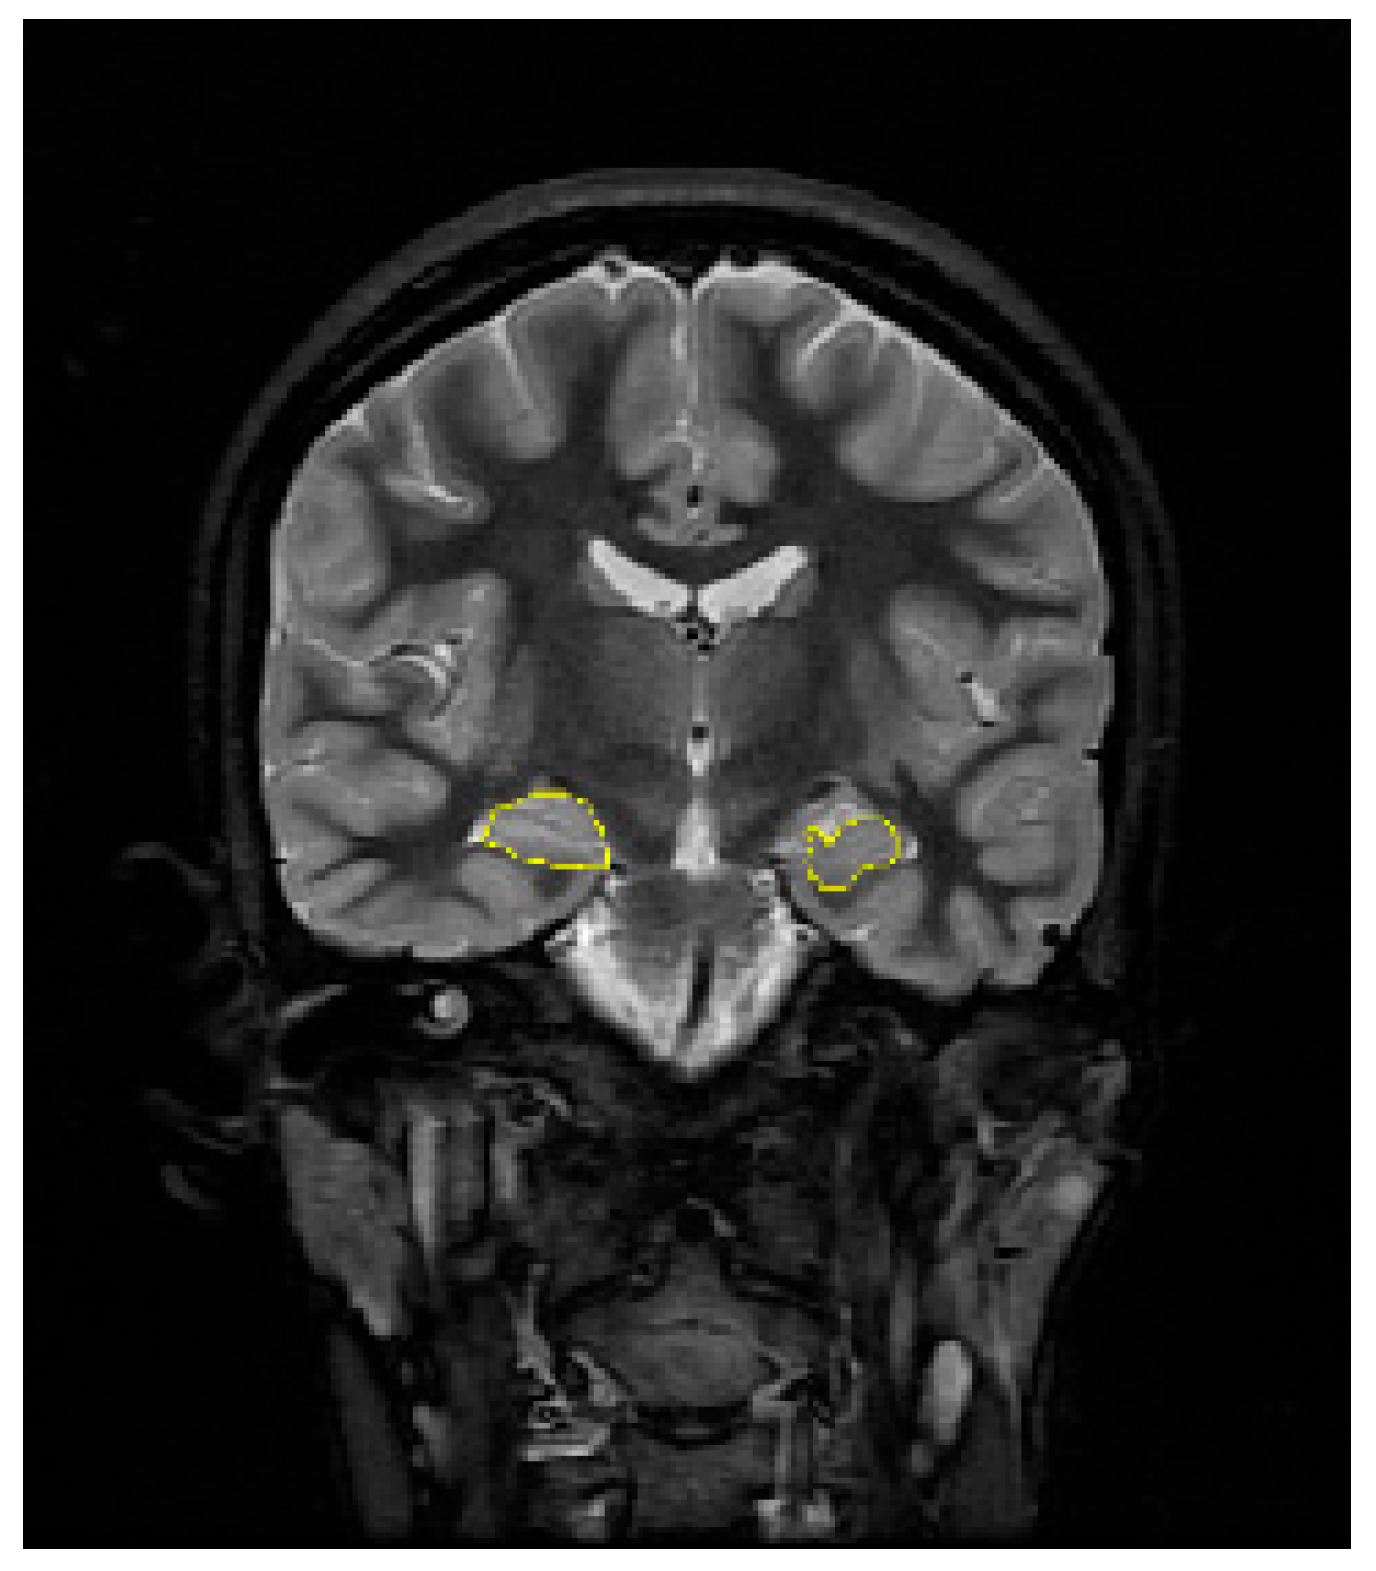

2.2. Hippocampal Volume Estimation and Pixel-Based Analysis of MR Images